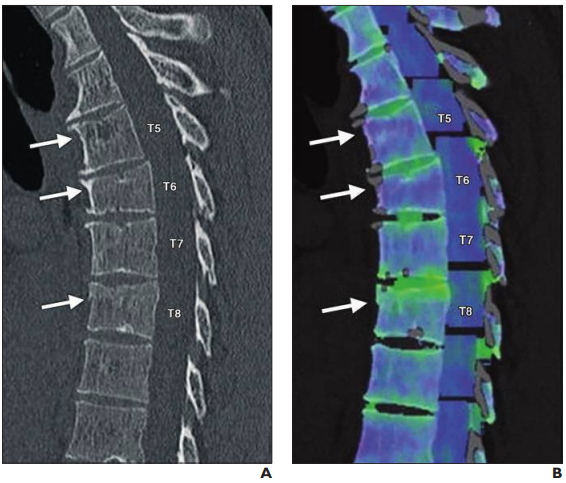

MRI offers high sensitivity and specificity, as well as positive and negative predictive value in detecting infection without the radiation.